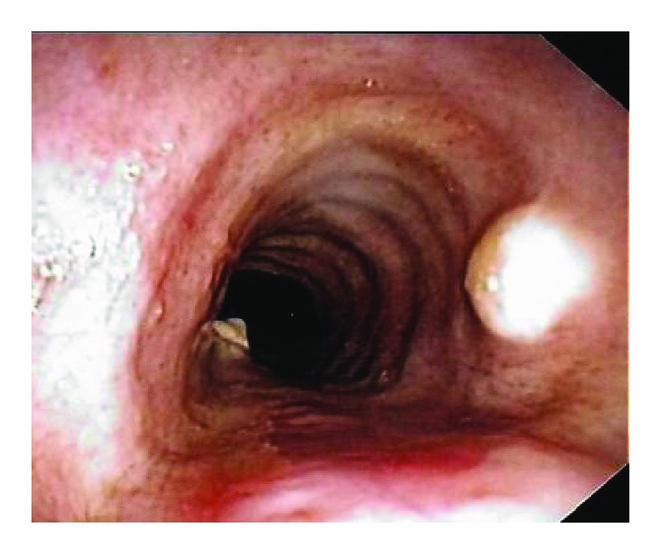

A bronchoscopy was performed which showed multiple flat white colored lesions in the trachea, left main-stem bronchi, right upper lobe bronchi (Figure 3), and a large polypoid, sessile, and white colored tumor located just distal to the secondary carina causing near-complete obstruction (>80%) of the right proximal bronchus intermedius (Figures 4 and 5). Several endobronchial biopsies were obtained from the large polypoid tumor located in bronchus intermedius and from the lesion in left main bronchus. Histopathological examination was consistent with granular cell tumor with tumor markers S-100 (Figure 6), Sox-10 (Figure 7), and CD-68 positive. Immunohistochemical analysis for pancytokeratin, cytokeratin 8/18, and synaptophysin was negative. Notably, sputum culture and right middle lobe bronchoalveolar lavage culture grew Streptococcus pneumoniae. The patient improved over the course of 4 days and was discharged home with a course of oral antibiotics for a total of 7 days, and follow-up was arranged in pulmonary clinic. However, patient was lost to follow-up.